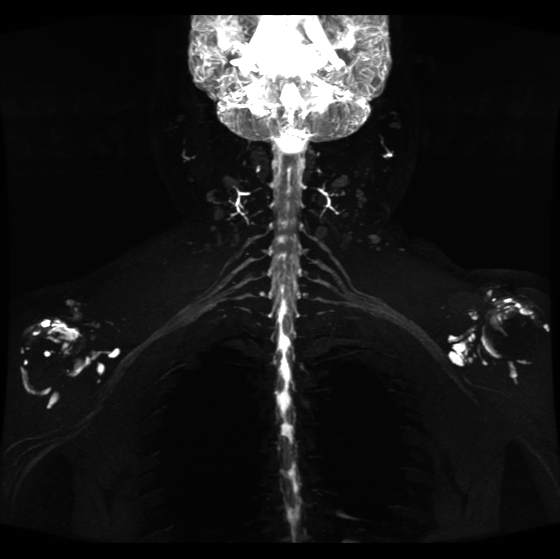

联影磁共振怎么样开启高精度诊断新模式!联影光梭3.0T磁共振落户周口市中心医院_https://www.jmylbn.com_新闻资讯_第3张

精准!高清晰度磁共振

让颈动脉斑块无处隐藏

最新一代联影光梭uMR790 3.0T 磁共振成像系统不仅可以显示血管狭窄程度、斑块大小和溃疡,还能提供斑块成分、纤维帽厚度和血管壁特征等易损性指标,已成为目前临床识别易损斑块最具有前景的辅助检查手段。